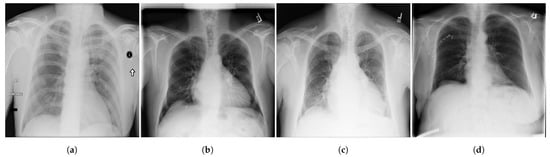

Figure 2.

Examples of CXR images from ChestX-ray14 dataset [39] where, (a) Nodule; (b) Emphysema; (c) Effusion; (d) Infiltration.